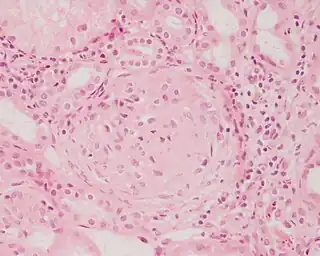

![]() Imagen histopatológica de una muestra de glomerulonefritis con semilunas obtenida de un paciente con glomerulonefritis rápidamente progresiva positiva para anticuerpos anti-MPO-ANCA. Tinción con hematoxilina y eosina. | ||

En la biopsia de estos pacientes se halla una importante proliferación de las células epiteliales de la cápsula de Bowman, con formación de semilunas en los glomérulos.[4] La biopsia renal confirma la presencia de una glomerulonefritis con semilunas epiteliales. Entre las características histopatológicas figura la infiltración del espacio urinario por células mononucleares asociada con la proliferación del epitelio parietal de la cápsula de Bowman o la proliferación extracapilar con formación de semilunas que pueden afectar del treinta al cien por ciento de los glomérulos. En estos se ve un engrosamiento de la cápsula de Bowman con formación de semilunas. También puede haber fibrosis parcial y sinequia del penacho glomerular a la cápsula.[4] Las semilunas, que pueden ser segmentarias o circunferenciales, ocupan todo el espacio de Bowman y ahogan el ovillo capilar, según el estado evolutivo pueden clasificarse en celulares, fibrocelulares o fibrosas y representan fases progresivas del mismo proceso.[4] En la glomerulonefritis rápidamente progresiva de tipo I hay positividad lineal sobre todo para IgG pero después también para C3. Dos tercios de las glomerulonefritis semilunares de este tipo corresponden al síndrome de Goodpasture y el otro tercio carece de manifestaciones pulmonares (síndrome de Goodpasture sin compromiso pulmonar). La lesión glomerular es similar en ambos grupos y se produce por un mecanismo inmunitario antimembrana basal glomerular. Como ya se dijo, el factor desencadenante es un defecto de un componente proteico de la cadena α3 del colágeno de tipo IV.[5] En la enfermedad de tipo II hay positividad granular o nodular o de ambas formas, difusa y global, debido a depósitos de complejos inmunes que con el microscopio electrónico se ven como depósitos densos. Este tipo por lo general corresponde a variedades de la glomerulonefritis aguda difusa, de la glomerulonefritis mesangiocapilar y, menos a menudo, de la enfermedad de Berger.[5]

Por último, en la glomerulonefritis semilunar de tipo III el examen con inmunofluorescencia es negativo y los hallazgos detectados con el microscopio electrónico son similares a los de la enfermedad de tipo I (sin depósitos densos). Si bien se ignora la patogenia de esta lesión glomerular, se piensa que en una buena cantidad de casos la causa de la ruptura de capilares glomerulares y de la proliferación celular glomérulo-capsular sería una vasculitis o una angiopatía. Este cuadro se observa con mayor frecuencia en adultos mayores.[5]